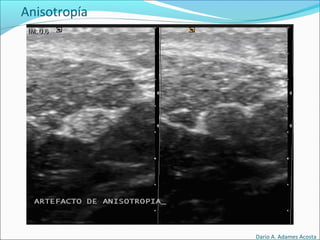

Anisotropía: Elementos que cambian ecogenicidad

dependiendo del ángulo desde donde se enfoque.

Anisotropía

• #47 ARTEFACTOS Reverberaciones Se producen cuando el haz de ultrasonidos incide sobre una interfase que separa dos medios de muy diferente impedancia acústica, como por ejemplo entre un sólido ecogénico y gas en el tubo digestivo o entre sólido y hueso. REFUERZO ACUSTICO POsTERIOR Se produce cuando el ultrasonido atraviesa un medio sin interfases en su interior y pasa a un medio sólido ecogénico. Es casi característica exclusiva de imágenes quísticas en el seno de estructuras sólidas. quiste renal en el que se aprecia un importante refuerzo acústico posterior SOMBRA ACÚSTICA Se produce cuando el ultrasonido choca con una interfase muy ecogénica y no puede atravesarla no detectándose ninguna imagen detrás de esta interfase tan ecogénica. Es muy característico de las litiasis biliares y renales y de las calcificaciones musculares. litiasis biliar , observamos como la señal hiperecogénica que corresponde a la litiasis deja una sombra COLA DE COMETA Ocurre cuando el haz de ultrasonidos choca contra una interfase estrecha y muy ecogénica apareciendo detrás de esta interfase una serie de ecos lineales. Es muy característico de los adenomiomas de pared vesical, cuerpos extraños muy ecogénicos y también pequeñas burbujas de aire en el seno de un medio sólido. adenomiomatosis de la pared de la vesícula biliar IMAGEN EN ESPEJO Se produce cuando una interfase muy ecogénica se encuentra delante de otra imagen curva tan ecogénica como ella produciéndose una sobra acústica posterior. hemangioma hepático cerca del diafragma que da una imagen igual extradiafragmática que es la imagen en espejo ANISOTROPIA Es la propiedad que tienen algunos tejidos de variar su ecogenicididad dependiendo del ángulo de incidencia del haz ultrasónico sobre ellos. La estructura anisotrópica por excelencia es el tendón. inserción tibial del tendón rotuliano y vemos que si la sonda no esta perpendicular nos da una falsa imagen de tendinitis, ya que se ve el tendón hipoecogénico

• #50 La anisotropía (opuesta de isotropía) es la propiedad general de la materia según la cual determinadas propiedades físicas, tales como: elasticidad, temperatura, conductividad, velocidad de propagación de la luz, etc. varían según la dirección en que son examinadas. Algo anisótropo podrá presentar diferentes características según la dirección. En un sentido más general, se habla de anisotropía cuando cualquier cambio de escala de una figura o un cuerpo, como en un gráfico x-y, se produce con factores distintos (o en dependencia de una función) en cada coordenada. Por ejemplo, en la autoafinidad que presenta el estudio de los movimientos de las Bolsas de valores, consideradas desde la autosimilaridad, desde sus propiedades fractales.